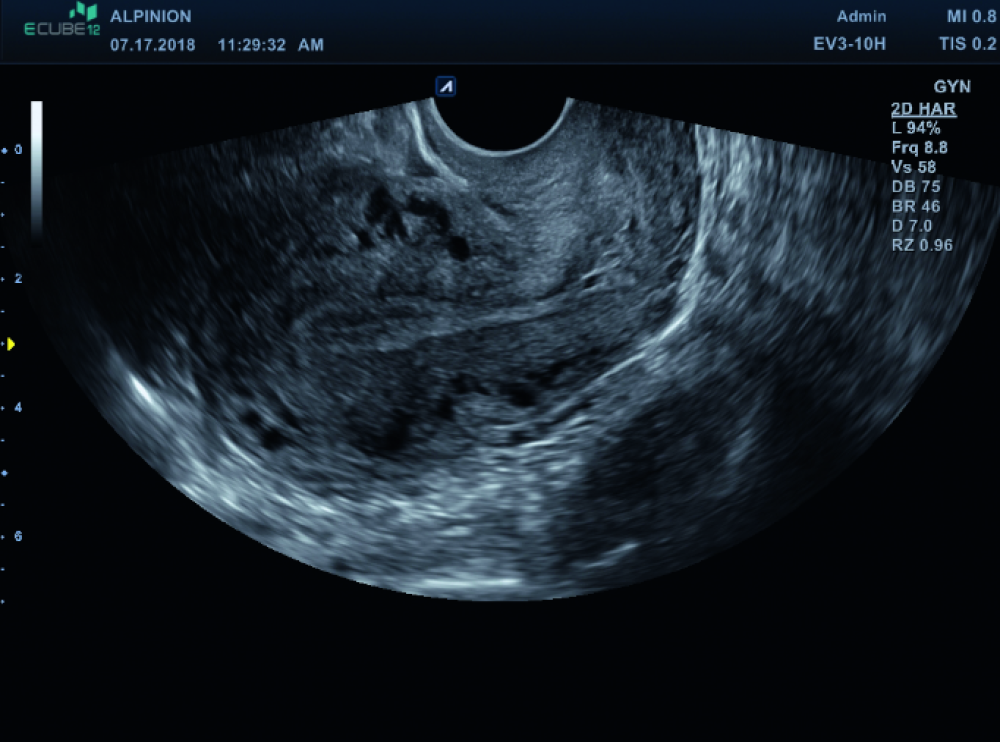

Moderne Frauenheilkunde stellt höchste Anforderungen an Bildqualität, Bedienkomfort und Vielseitigkeit. ALPINION unterstützt Gynäkologinnen und Gynäkologen mit leistungsstarker Ultraschalltechnologie, die sowohl im Praxisalltag als auch im klinischen Umfeld überzeugt. Unsere Systeme liefern hochauflösende Bilder bei transabdominaler und transvaginaler Sonografie – für eine sichere, schnelle und präzise Diagnostik in allen Phasen der Frauengesundheit.

• Kristallklare Bildgebung – auch bei feinsten Strukturen

• Erweiterte Doppler-Technologie zur Gefäßdarstellung und Beurteilung pathologischer Befunde